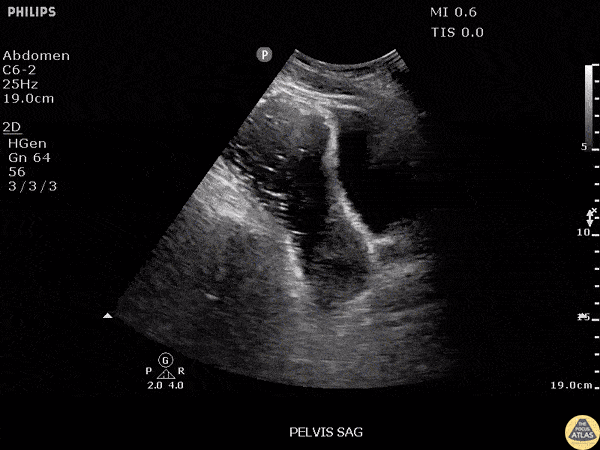

Bowel-GI - Pelvic Free Fluid in Ruptured Appendicitis

Free fluid is noted in this clip from the pelvic region during a RUSH exam in a patient with a ruptured appendicitis. Image courtesy of Robert Jones DO, FACEP @RJonesSonoEM Director, Emergency Ultrasound; MetroHealth Medical Center; Professor, Case Western Reserve Medical School, Cleveland, OH View his original post here